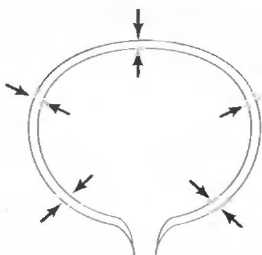

Форма среза, получаемая при использовании различных датчиков

1. Линейный датчик. Срезы при использовании таких датчиков имеют форму прямоугольников. Эти датчики наиболее удобны в акушерских исследованиях, а также при исследовании щитовидной и молочных желез (рис. 7а).

Рис.7а. Срезы прямоугольной формы, получаемые при использовании линейного датчика.

2. Секторный датчик. Срезы имеют форму веера, почти треугольного. Эти датчики удобно использовать при наличии очень небольшого по площади, доступного для исследования пространства. Они используются для исследования верхних отделов брюшной полости, а также в гинекологии и кардиологии (рис. 76).

Рис.7б. Срезы в форме веера, получаемые при использовании секторного датчика.

3. Конвексный датчик. Получаемый срез имеет форму, промежуточную между формой среза линейного и секторного датчиков, и используется для сканирования всех частей тела, кроме эхокардиографии (рис. 7в).

Рис.7в. Широкополосный веерообразный срез с широкой, изогнутой вершиной отконвексного датчика.